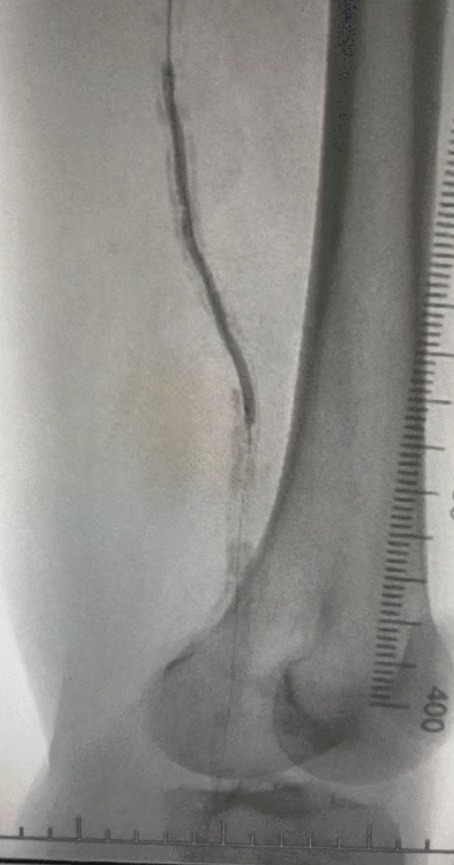

· Imaging preoperatorio: stenosi calcificata grave e diffusa nelle arterie degli arti inferiori bilaterali

Data la complessa condizione vascolare, abbiamo selezionato il sistema di catetere di dilatazione del palloncino IVL periferico ThorCrack. A causa della tolleranza limitata del paziente, sono state eseguite procedure interventistiche in scena su entrambi gli arti inferiori.

Esito chirurgico

Dopo la procedura, la stenosi arteriosa è migliorata in modo significativo, il flusso sanguigno è aumentato e la temperatura della pelle è aumentata. Non si sono verificate complicanze postoperatorie. Sia il paziente che il team chirurgico sono stati molto soddisfatti dei risultati.